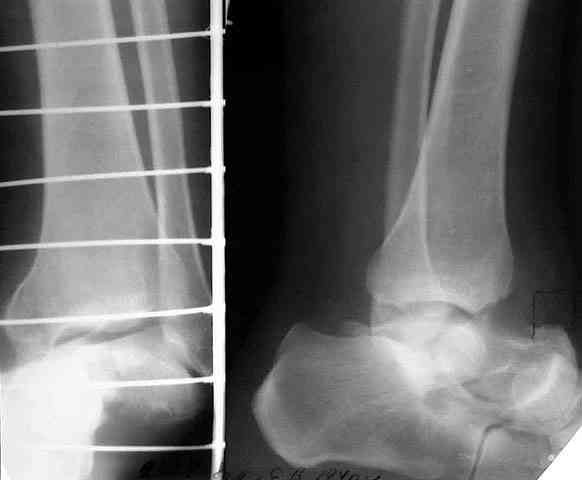

> кости. Выполнена ПХО, фиксация голени и стопы стержневым аппаратом.

> Рана зажила без осложнений. Аппарат демонтирован через 1,5 месяца.

Учитывая ликвидацию голеностопного и подтаранного суставов, надо поберечь остающиеся, чтобы рессорную функцию стопы сохранить по максимуму. Поэтому лучше избегать всякого рода дополнительных вмешательств поблизости от ТЛ и ПК суставов, а то на некоторых схемах чуть ли не их замыкание предусматривается. Опил большеберцовой кости

нарисован слишком горизонтальный, надо пересекать ее параллельно контактной поверхности пятки, наклонно, т.е. больше убрать сзади.